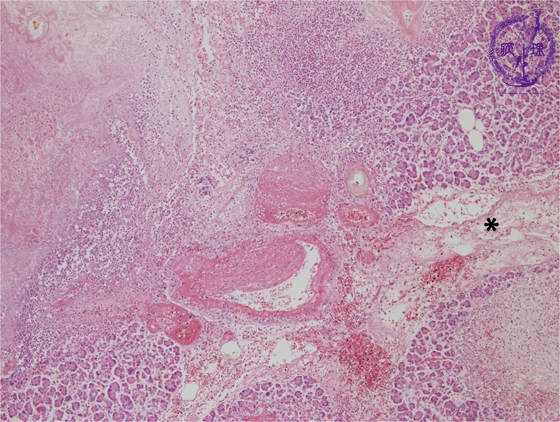

Microscopic image(HE stain, low power):There is destruction of interlobular blood vessels with pancreatic parenchymal necrosis. The majority of inflammation is seen within the pancreatic parenchyma.The interlobular space (*) shows edema and lymphectasia.